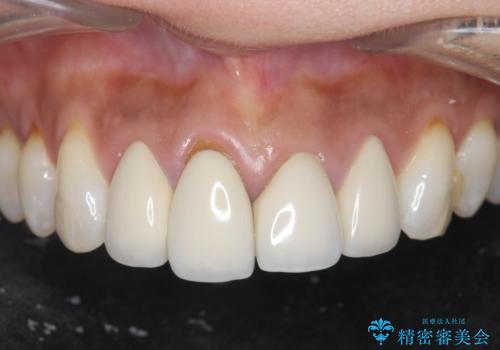

[メタルフリー] 虫歯・銀歯だらけの口腔内を全顎治療

![[メタルフリー] 虫歯・銀歯だらけの口腔内を全顎治療の症例 治療前](https://seimitsushinbi.jp/wp/wp-content/uploads/2025/03/e26a9887bc6905a2f0f51f5772b5ac9c-500x350.jpg?v=1741918285)

![[メタルフリー] 虫歯・銀歯だらけの口腔内を全顎治療の症例 治療後](https://seimitsushinbi.jp/wp/wp-content/uploads/2025/03/530cf6cca6451bc106a9fb69dd58908a-500x350.jpg?v=1741918343)